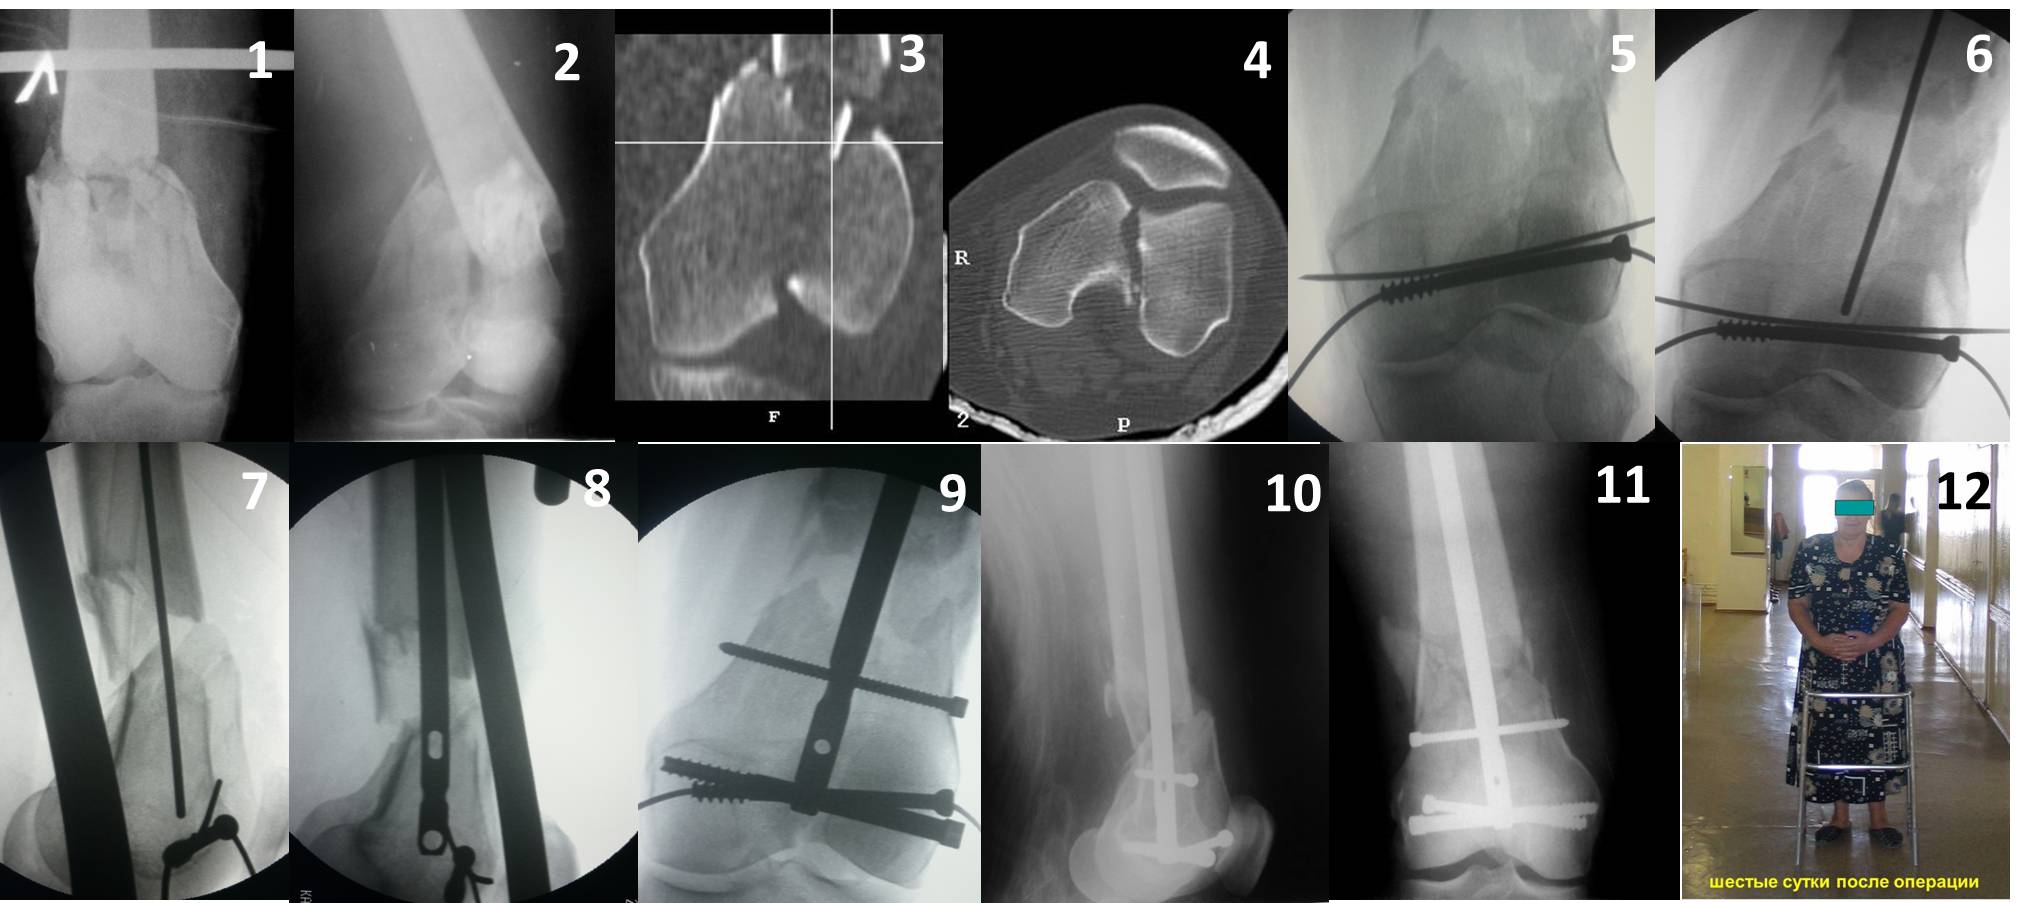

В приложении пример недавней операции, C3, открытая репозиция, фиксация мыщелков спицами и винтами, ретроградный синтез большеберцовым гвоздем 10,5 мм диаметром, винты 5 мм.

Ответ на эту часть Вашего поста – вложенный файл. Больная оперирована неделю назад по поводу открытого перелома дистального эпиметафиза бедренной кости. После операции она идёт в рентгенкабинет для выполнения послеоперационной контрольной рентгенографии, представленной на слайдах 10 и 11. Узнав, почему её фотографируют, просила передать Вам, Антон, привет.